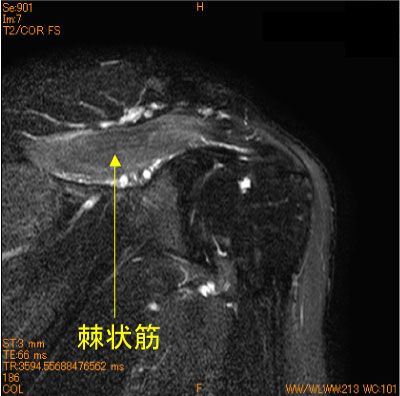

腕神経叢炎(Peronage-Turner 症候群)-肩関節MRI-

20代男性、疼痛肩、脂肪抑制T2 high changeを三角筋(腋窩神経)、棘上筋、棘下筋(肩甲上神経)を認めている。

神経原性筋浮腫であるが、異なる神経支配領域の筋肉群に変化を認めている。

![]() Obl. Cor T2WI 脂肪抑制 |